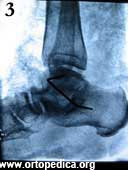

3. Рентгенограмма в боковой проекции после операции подтаранного артродеза

Рентгенограмма в боковой проекции после операции подтаранного артродеза Рентгенограмма после операции подтаранного артродеза Рентгенограмма через 2 месяца после операции подтаранного артродеза